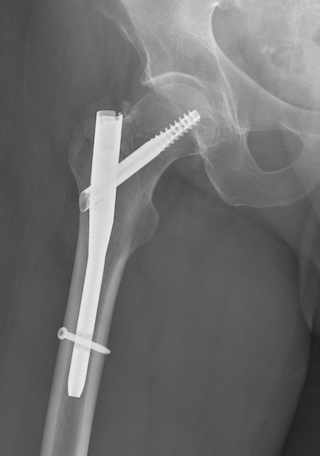

Kalça kırıkları, kalça kemiğinin çeşitli nedenlerle kırılması durumudur. Genellikle düşme, trafik kazaları veya kemik erimesi (osteoporoz) gibi durumlar bu kırıklara yol açar. Özellikle ileri yaşlarda kemik yoğunluğunun azalmasıyla bu tür kırıkların riski artar. Kalça kırığı, kişinin yürüme, oturma ve günlük aktivitelerini yapma yeteneğini ciddi şekilde etkiler. Bu nedenle, kırık sonrası iyileşme sürecinde rehabilitasyon programı büyük bir önem taşır. Rehabilitasyon, kas gücünü geri kazanmayı, hareket kabiliyetini artırmayı ve olası komplikasyonları önlemeyi hedefler. Doğru bir program olmadan, kişi uzun süreli hareketsizlik nedeniyle ek sağlık sorunlarıyla karşılaşabilir.

- Ağırlık Taşıma Eğitimi: Doktorun onayıyla, kırık bölgesine kontrollü bir şekilde ağırlık verilmeye başlanır. Bu süreçte koltuk değneği veya walker gibi destekleyici araçlar kullanılır. Amaç, kalça bölgesindeki kasları güçlendirmek ve normal yürüme düzenine dönmektir.